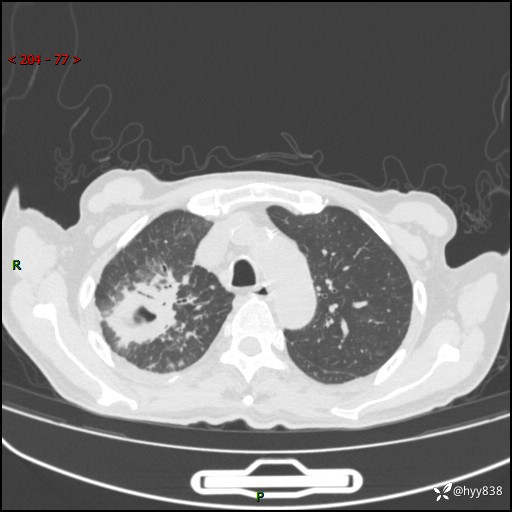

第一次胸部CT检查